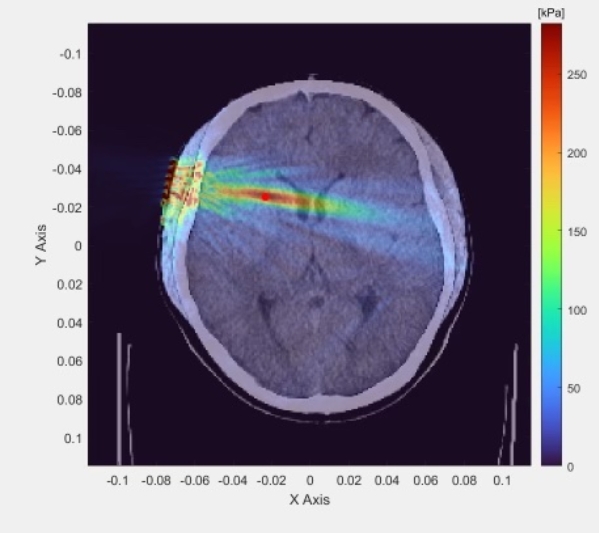

AI控制梦境成真了,你也能随时做一个清醒梦。 最近,一款由美国Prophetic AI公司开发的革命性AI系统,它正将梦境控制变为可能! Morpheus-1运用先进的超声波技术,精准刺激你的大脑,模拟自然清醒梦的电活动,让你在梦中也能保持清醒的意识。 配合Halo头带,内置传感器和微型计算机实时监测你的脑电波,AI系统智能调整,定制你的个人梦境体验。 在不需要侵入性手术的情况下,通过精准的神经感知技术和AI系统实现可控的梦境意识工程,这不仅仅是一场新奇的体验,Morpheus-1旨在深化我们对睡眠和潜意识的理解,释放梦境的无限潜力。这才是真正的元宇宙啊。 清醒梦AI系统Morpheus-1的诞生,标志着人类对梦境探索的新纪元。当科技与梦境交织,将创造出怎样的奇迹呢? 在梦中,你也可以是造物主!